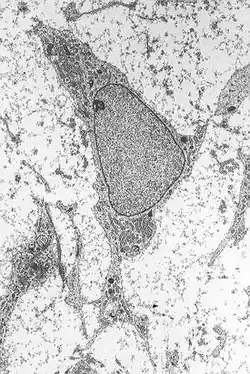

A mesenchymal stem cell